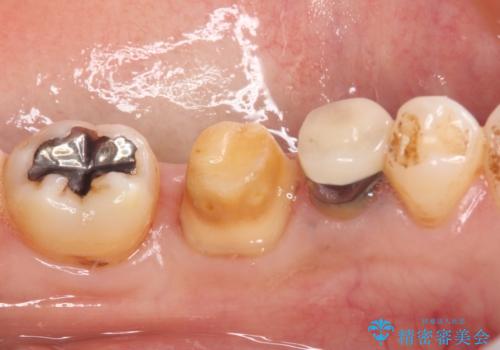

知覚過敏の症状はなくなり、希望通りの白い歯になったと、患者様は大変満足されました。

知覚過敏の症状が強い歯と、銀歯の範囲や銀歯の下のむし歯が大きい歯は、インレー修復では対応が難しいためオールセラミッククラウンで、インレー修復で対応が可能な歯ではセラミックインレーにて修復することとしました。